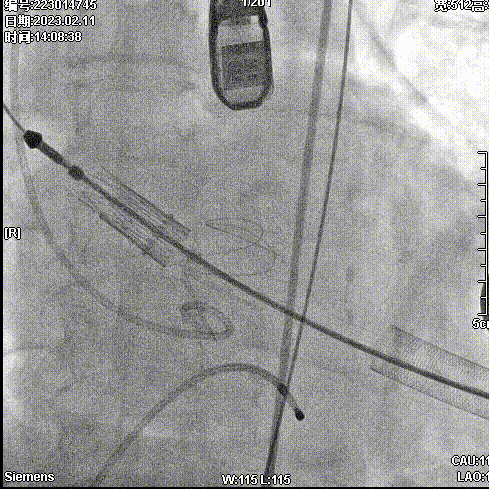

2月11日,新疆维吾尔自治区人民医院杨毅宁教授团队成功应用J-Valve完成两例具有挑战性的横位心TAVR病例。其中一例为窦部扩张+横位心,另外一例为升主动脉增宽+横位心,且两例患者均为主动脉瓣关闭不全(反流)。

病例一:窦部扩张与横位心

手术步骤

拔除股动脉血管鞘,缝合股动脉。手术顺利结束。